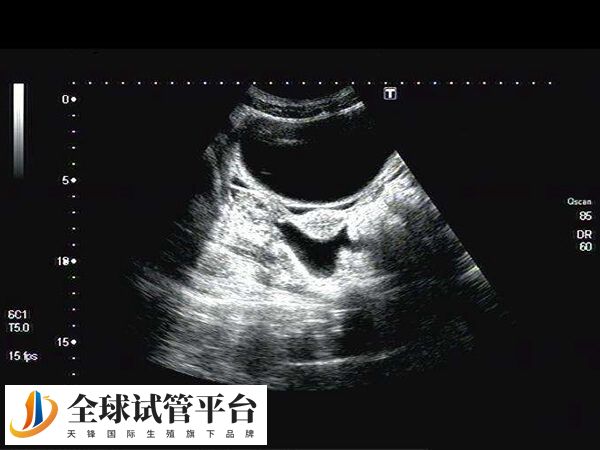

子宫内膜形态主要分为三型,A型为三线型子宫内膜,B型为弱三线型,C型为均匀强回声,这三种形态是月经不同阶段的影像表现。通常阴道B超提示为典型的三线型子宫内膜更适合移植,这样有助于提高胚胎着床率。